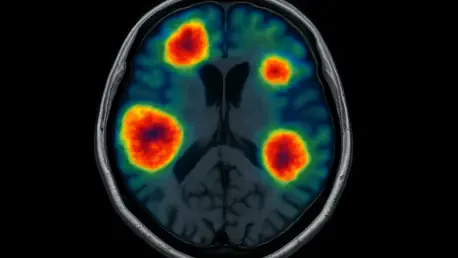

Imagine a scenario where a patient, battling cancer that has spread to the brain, undergoes complex treatments like radiation or chemotherapy, only to face uncertainty when follow-up scans can’t clearly show whether the tumor is growing or if the changes are just treatment side effects. This diagnostic dilemma is all too common in managing brain metastases, a devastating complication affecting many with solid tumors such as lung or breast cancer. The stakes are incredibly high—misdiagnosis can lead to unnecessary surgeries or delayed critical care, impacting survival and quality of life. Enter 18F-Fluciclovine PET/MRI, an imaging innovation originally developed for prostate cancer, now showing promise in distinguishing true tumor progression from treatment-related changes in the brain. With early research revealing a remarkable 91% accuracy rate, this tool could redefine precision in neuro-oncology. This article explores the challenges of current methods, the science behind this tracer, its performance in real-world cases, and what lies ahead for its integration into clinical practice, shedding light on a potential breakthrough for patients and clinicians alike.

18F-Fluciclovine, an amino acid-based imaging agent initially approved by the FDA for detecting recurrent prostate cancer, operates on a unique principle that makes it particularly suited for identifying active tumor tissue in the brain during PET/MRI scans. Tumor cells, which often have a heightened uptake of amino acids due to rapid growth, absorb this tracer at a higher rate than surrounding healthy brain tissue, creating a stark contrast visible on imaging. This high tumor-to-brain contrast is a key advantage over conventional methods, allowing for more precise identification of disease progression even after treatments like radiation or immunotherapy that can obscure standard scans. The adaptation of this agent for brain metastases marks an innovative repurposing of existing technology, driven by the urgent need for better diagnostic tools in neuro-oncology, where distinguishing true recurrence from treatment effects remains a persistent challenge.

The performance of 18F-Fluciclovine PET/MRI in distinguishing brain metastases progression from treatment effects stands out with a reported accuracy of 91%, a figure that suggests a significant leap over traditional imaging methods. Equally striking is its 100% sensitivity, meaning it successfully identified every instance of true progression in the studied cases, a critical factor in ensuring no patient misses timely intervention. The perfect negative predictive value further reinforces this reliability, indicating no false negatives were recorded, while a specificity of 89% shows a strong ability to rule out progression when it isn’t present. However, a positive predictive value of 67% points to a moderate rate of false positives, an area where refinement is needed. These metrics, derived from a detailed analysis of patient scans, highlight the tracer’s potential to transform diagnostic confidence in neuro-oncology.